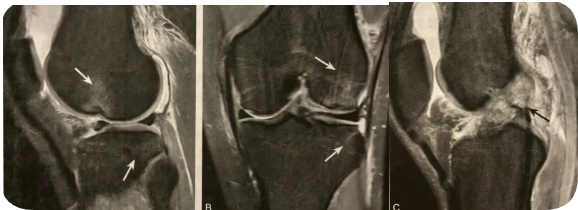

1. 半月板桶柄样撕裂的影像学表现;

2. 在 MRI 矢状位观察;

3. 至少两个不同层面 MRI 矢状位领结影消失,特异性较高;

4. 当领结消失征和其他碎片移位征象联合时,特异性明显提高。